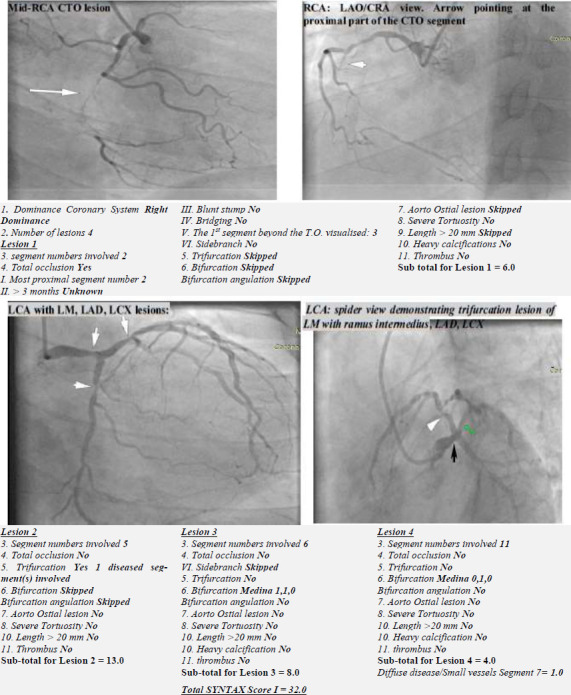

Intervention: The patient's angiograms were analysed, and the CAD severity was obtained using the SYNTAX scoring criteria.

Main outcome measure: The lesion overall severity (SYNTAX) score and the relationship with CVRFs present.

Results: out of the 169 patients that had coronary angiography, 78 had significant CAD. The mean SYNTAX score was 20.18 (SD= 10.68), with a significantly higher value in dyslipidaemic patients (p < 0.001). Pearson's correlation between the score and BMI was weak (r= 0.256, p= 0.034). The occurrence of high SYNTAX score lesions in about 18% of the population was significantly associated with hypertension (OR= 1.304, 95% CI [1.13-1.50]; p= 0.017) dyslipidaemia (OR= 5.636, 95% CI [1.17-27.23]; p= 0.019), and obesity (OR= 3.960, 95% CI [1.18-13.34]; p= 0.021). However, after adjusting for confounding factors, only dyslipidaemia significantly influenced its occurrence (aOR= 5.256, 95% CI [1.03-26.96]; p= 0.047).